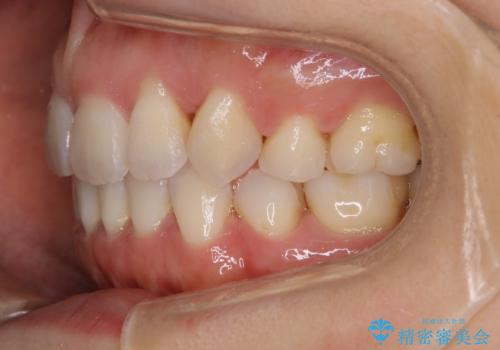

- 笑った時の歯の見え方を治したいとのことで矯正相談にいらっしゃいました。

一見そこまで大きなガタつきはないようにも見えますが、前歯の角度の不揃いや噛み合わせのズレなどから見え方に影響が出てしまっていました。

抜歯は全く必要のないレベルのガタつきだったため、マイクロインプラントを用いて歯全体を後方に移動させていくことできれいな歯並びを獲得することができました。